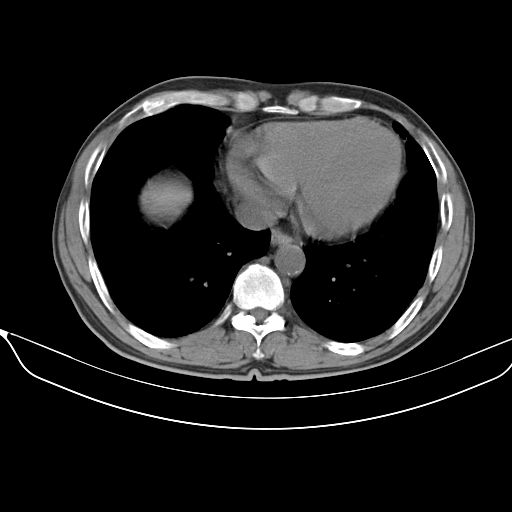

以下是引用心路寻觅在2010-3-1 10:23:00的发言:[br]1、考虑左肺上叶周围型肺癌[br]2、右上肺陈旧性病灶。[br][br][本贴已被 心路寻觅 于 2010-3-1 10:40:18 修改过]

以下是引用shuiyuan在2010-3-1 10:45:00的发言:[br]考虑左肺上叶中心型肺癌伴阻塞型炎症,邻近胸膜受侵。